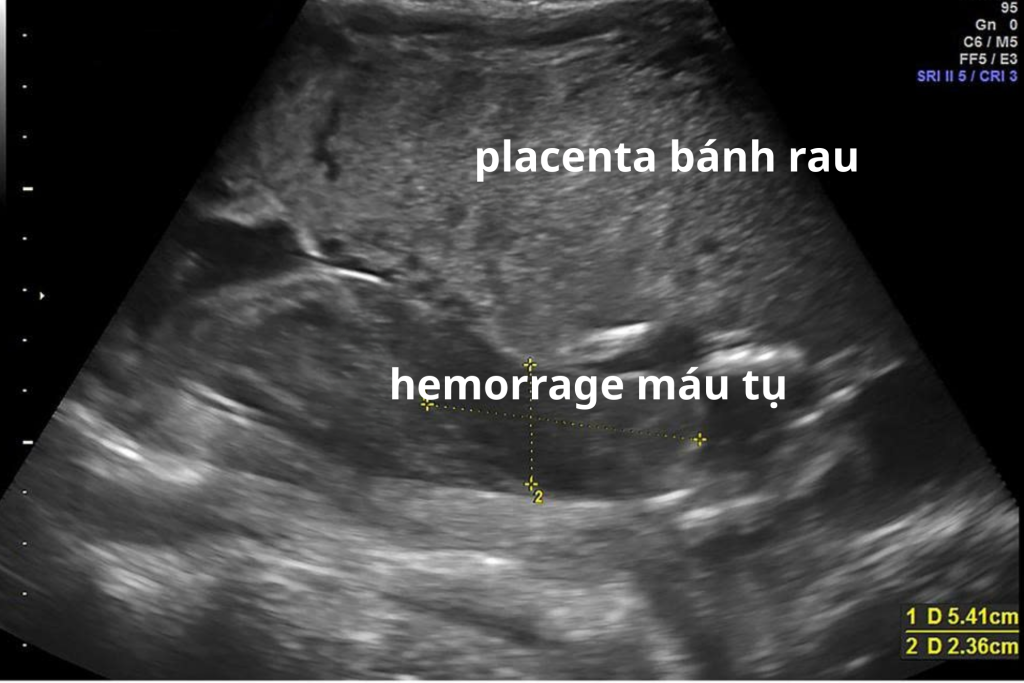

Vai trò của siêu âm trong xử lý nhau bong non

Siêu âm có thể hỗ trợ phát hiện:

• Khối máu tụ sau bánh nhau

• Bánh nhau dày bất thường

Tuy nhiên, siêu âm không loại trừ hoàn toàn nhau bong non nếu hình ảnh chưa rõ. Chẩn đoán chủ yếu dựa vào lâm sàng.